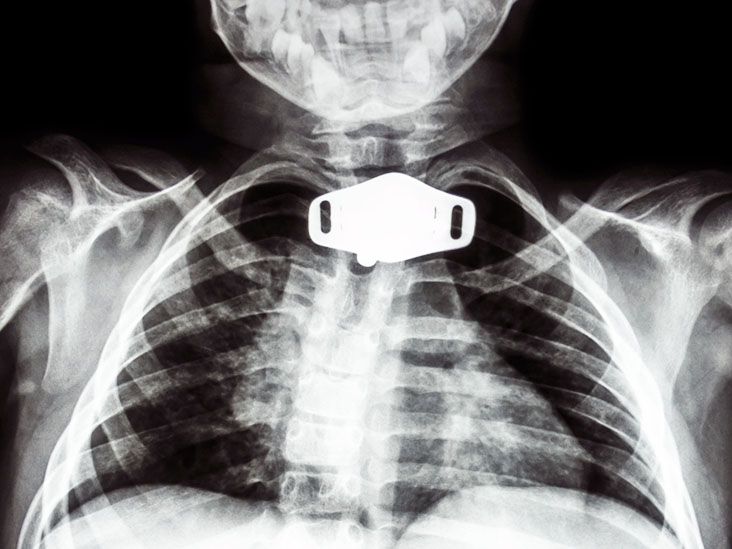

Tracheostomy Uses, procedure, and complications Tracheostomy Quality Of Life Insertion of a tracheostomy tube has a significant impact on the quality of life of the patient and the amount of burden increases. Quality of life* respiration, artificial* surveys and questionnaires. Patients with tracheostomy were less likely discharged at home but at hospital facilities or rehabilitative structures; Some patients with a tracheostomy are able to go home. Tracheostomy / nursing*. Tracheostomy Quality Of Life.